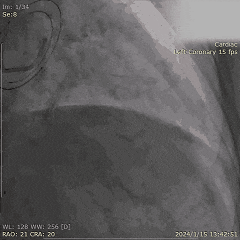

Step 3. 主动脉根部及冠状动脉造影

Step 4. 行PBMV术治疗